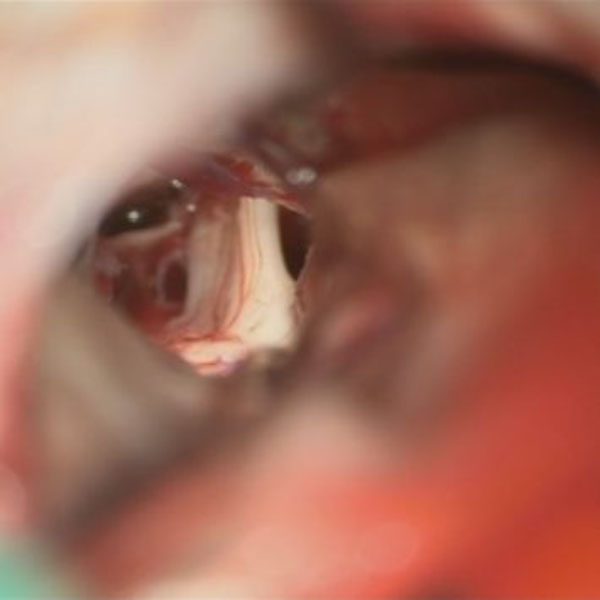

症例 '26年4月

No.

590

当院外来

'26年4月

60代

三叉神経痛第3枝領域

(顔面の痛みをとること)

手術前

減圧前

減圧後

術後血管撮影